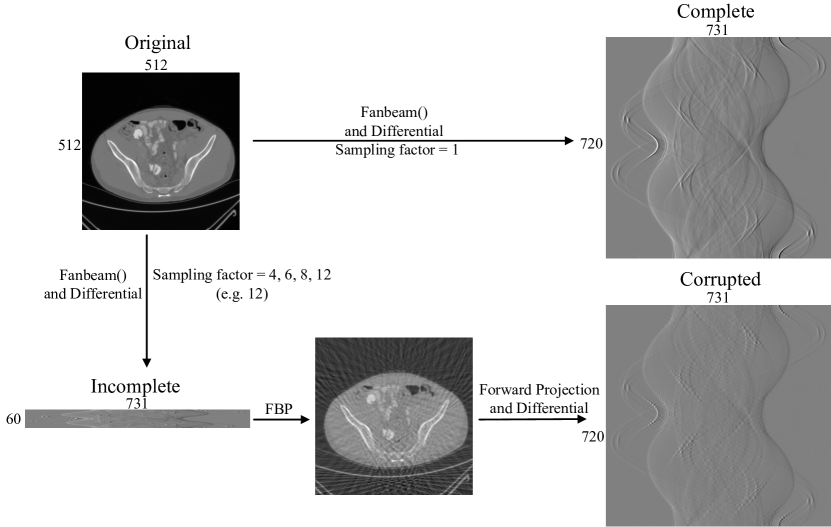

III-A Data preparation

III-A1 Synthetic

For synthetic data sets, 500 phantoms are used to obtain the fan beam phase-contrast sinograms with different sampling factors. Each phantom consists of tens of ellipses with random refraction coefficients, size, and location. And the sampling factors are set to be 1, 4, 6, 8 and 12. They correspond to 720, 180, 120, 90 and 60 views, respectively. The size of each phantom is 512×512512512512\times 512 pixel. Fan beam sinograms are generated by using the embedded MATLAB function fanbeam()𝑓𝑎𝑛𝑏𝑒𝑎𝑚fanbeam\left({}\right). The width of all the sinograms are 731 pixels. The sinogram with sampling factor 1 has a size 720×731720731720\times 731 pixel and is treated as complete one. Other sinograms are incomplete. Sinograms of 400 phantoms are used to train the framework and those from another 100 phantoms are used to test the framework.

Within the framework, for each incomplete sinogram, the initial FBP reconstruction is firstly executed with Eq.(2) and Eq.(3) to obtain the initial DPC-CT image. Then the forward projection operator in Eq.(4) and the differential method in Eq.(1) are applied to the initial DPC-CT image to generate the corresponding corrupted phase-contrast sinogram with a size 720×731720731720\times 731 pixel. Next the iterative deep learning runs to update the network parameters by making comparison between the corrupted and the complete phase-contrast sinogram.

After that, all the operations and procedures are the same as the ones for synthetic data sets. Fig. 3 is an example of how to prepare the training and testing data.

Refer to caption

Figure 3: An example of how to prepare the training and testing data.